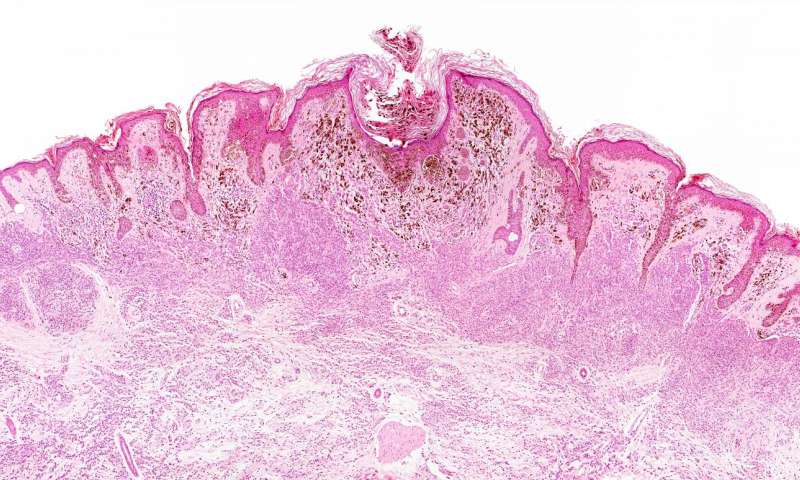

Il gruppo di Perera ha già dimostrato che sprightly è presente a livelli elevati nelle cellule di melanoma e che abbassare i livelli della molecola favorisce la morte delle cellule tumorali. I ricercatori hanno scoperto che i livelli di sprightly e altri lncRNAs sono elevati nel cancro prostatico rispetto al tessuto normale, suggerendo che la molecola potrebbe essere un marker diagnostico o prognostico del tumore.

Gli scienziati hanno poi usato CRISPR / Cas9, un metodo di modifica genomico recente, per ridurre l’espressione di sprightly nelle cellule di melanoma ed hanno trovato che i livelli della maggior parte dei suoi sei partner principali erano stati ridotti. Inoltre, in un modello murino di melanoma immunocompromesso, i tumori con solo una piccola quantità di sprightly sono cresciuti molto più lentamente rispetto ai tumori con livelli più tipici di RNA.